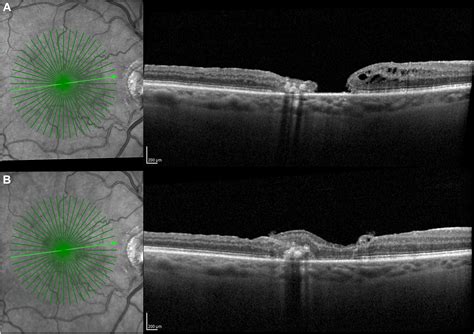

Preparation is key to a smooth surgical experience. Before your surgery, your doctor will perform a thorough examination, including an Optical Coherence Tomography (OCT) scan, which provides high-resolution images of the macular hole. You should discuss all current medications with your healthcare provider, especially blood thinners, and arrange for someone to drive you home after the procedure. Ensuring your home environment is set up for your recovery period will also help you feel more at ease once you return home.